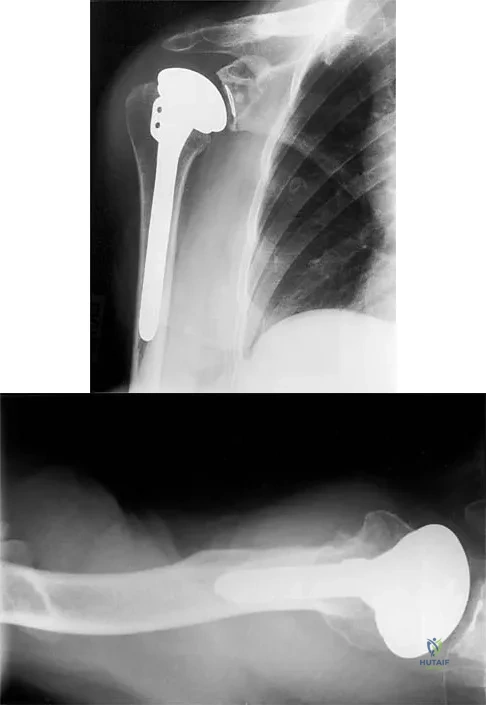

A 54-year-old man undergoes total shoulder arthroplasty for osteoarthritis. Despite compliance with an early passive range-of-motion exercise program, he does not regain more than 90 degrees of elevation, 10 degrees of external rotation, and has internal rotation to the fifth lumbar vertebra. At 6 months, his motion fails to improve. Radiographs are shown in Figures 18a and 18b. What is the best course of action?

A 72-year-old man has had persistent pain after undergoing a hemiarthroplasty 18 months ago. Radiographs are shown in Figures 50a and 50b. What is the most likely cause of his problem?